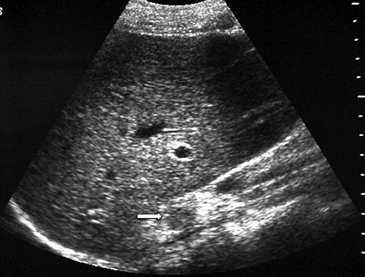

Figura 6. Lesión homogénea, de contornos bien delimitados (flecha) visualizada en tomografía computada sin contraste realizada en contexto de estudio de diseminación de cáncer mamario. A pesar de los caracteres morfológicos aparentemente benignos, se demostró que la lesión correspondía a una localización secundaria.